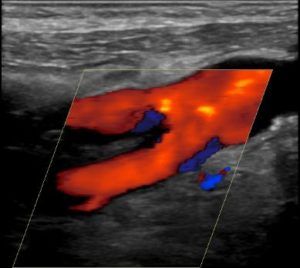

The diagnosis is usually incidental. Typically, we order carotid artery imaging for another reason. Obviously, the most common imaging we use is carotid artery ultrasound. Even if the focus of the study are the internal carotid arteries, we can see the external arteries easily: